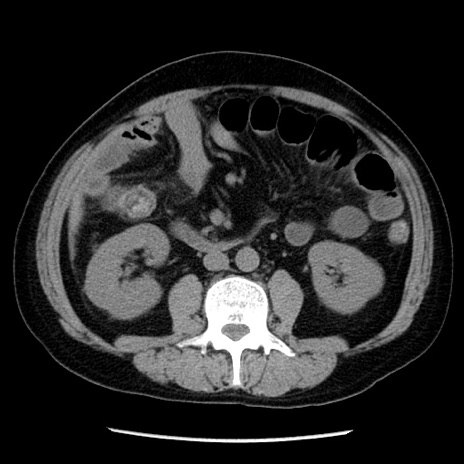

冠状断像

【症例】40歳代男性

【現病歴】2日前から胃痛あり。徐々に周期的な激痛に変化した。本日になっても激痛があるため受診。

【身体所見】意識清明、BT 38-39℃台あり、腹部:膨満、やや硬、右下腹部に圧痛あり。

【データ】WBC 8500、CRP 23.26